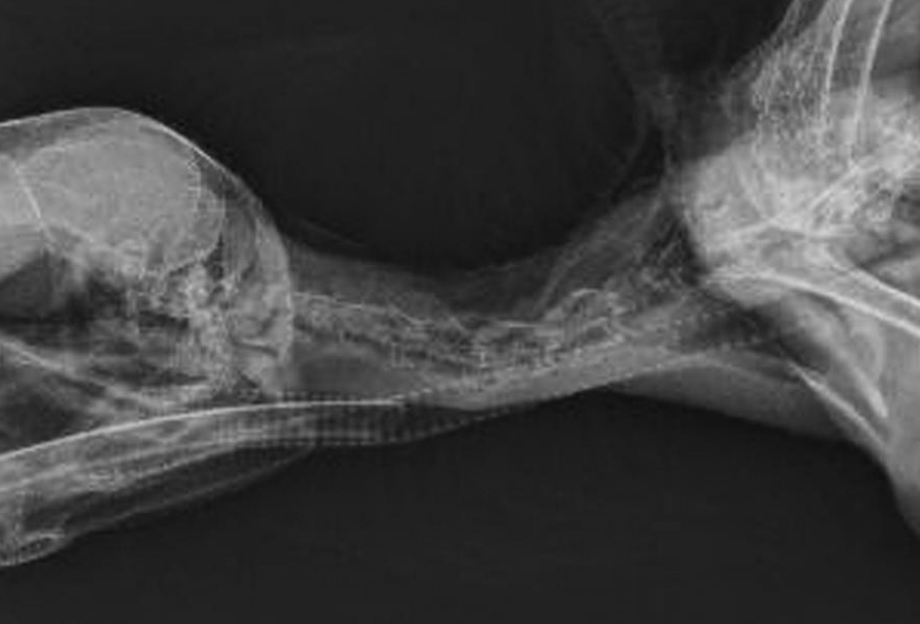

Which two birds have pneumatized ulnas, meaning only the proximal tibia can be used for IO fluid administration?

Which bone is used for IO fluid administration most often, except in Condors and Pelicans?